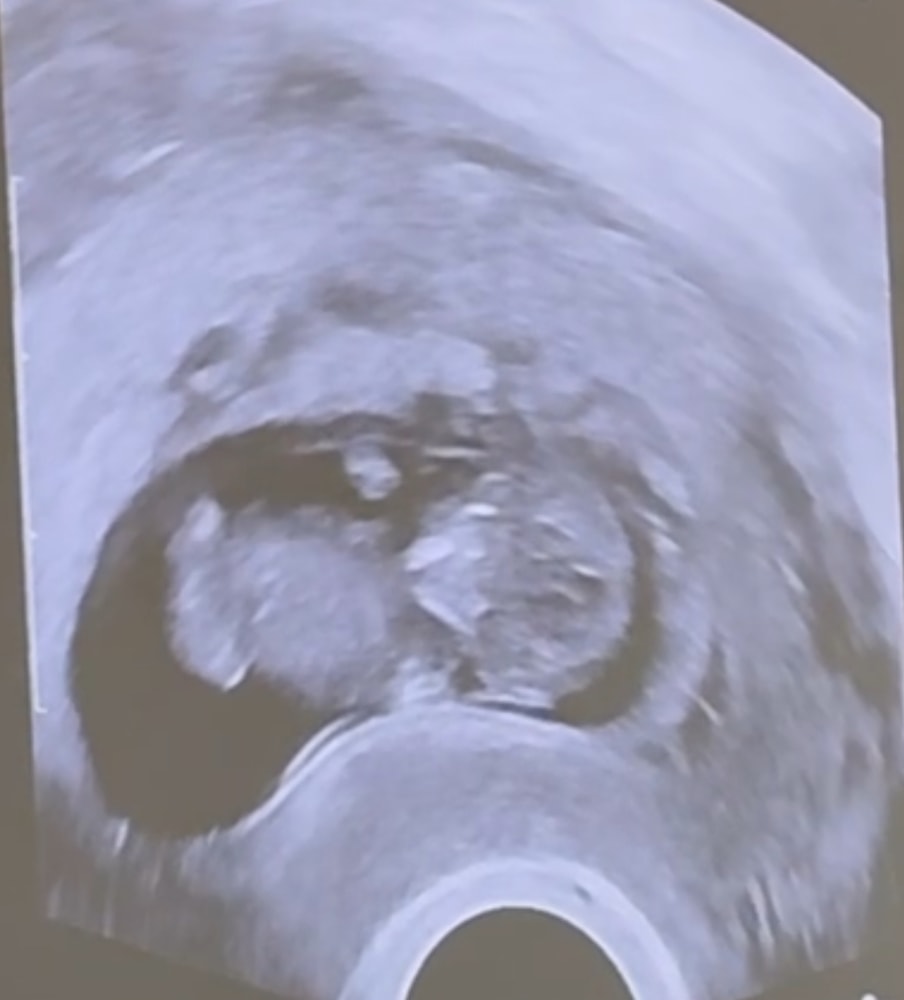

Добрый день! Это он в кружочке? 🥹

Юлия Крас, вот он! Размером со сливу уже!) Изображение